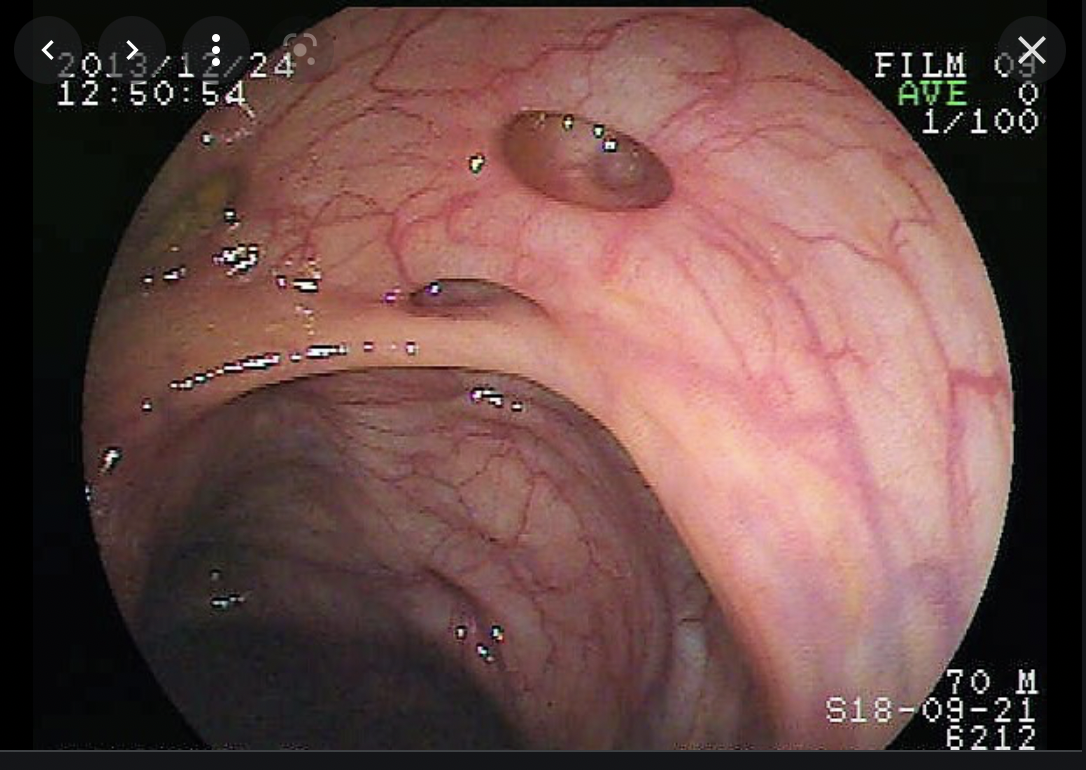

גסטרוסקופיה- משמשת לאבחון וחיפוש קרישי דם (במטופל יציב נזיז אותו כדי לראות מה שוכן מתחת). יש גם אמצעים לעצירת דימום- פרובים שמחממים את הרקמה ומביאים לקואגלציה, הזרקת סיילין ואדרנלין כדי להפעיל לחץ על הכלי המדמם, קליפסים, קשירה של הדליות.